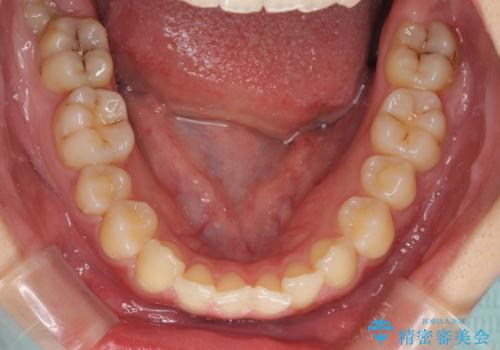

- 上下前歯のデコボコを気にして来院された患者様です。

以前矯正をした後戻りということで、歯列不正はそれほど大きくなかったため、インビザライン・ライトを用いて矯正治療を行うこととしました。

前歯のデコボコが残っており、シミュレーション通りに動いていない部分がありましたが、再矯正であることやご本人の満足いくところまでデコボコが改善されたとのことで、治療を終了することとしました。